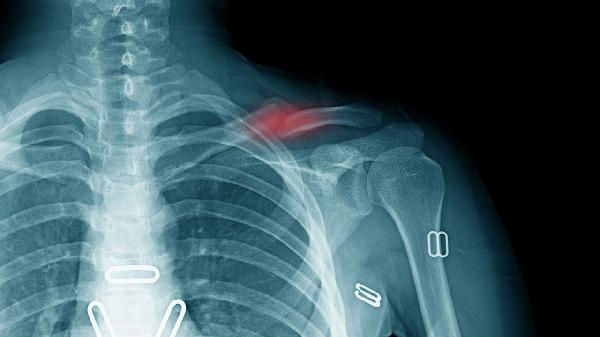

5、锁骨骨折

外伤后出现的剧烈疼痛、肿胀需警惕骨折可能。X线检查可明确诊断,不完全骨折可用锁骨固定带制动,完全移位骨折需手术内固定。恢复期遵医嘱使用接骨七厘片、伤科接骨片等药物,配合红外线照射促进骨痂形成。